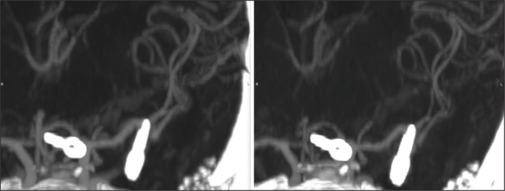

Remote cerebral vasospasm following elective clipping of middle cerebral artery bifurcation-A1 aneurysms: A correspondence and review of putative pathophysiological mechanisms.

选择性切断大脑中动脉分叉a1动脉瘤后的远端脑血管痉挛:对假定病理生理机制的对应和回顾